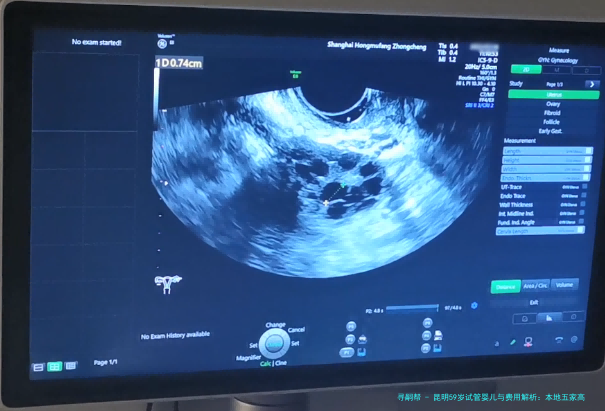

阴道B超监测排卵15080110100/次

抗缪勒管(AMH)检测500300380350